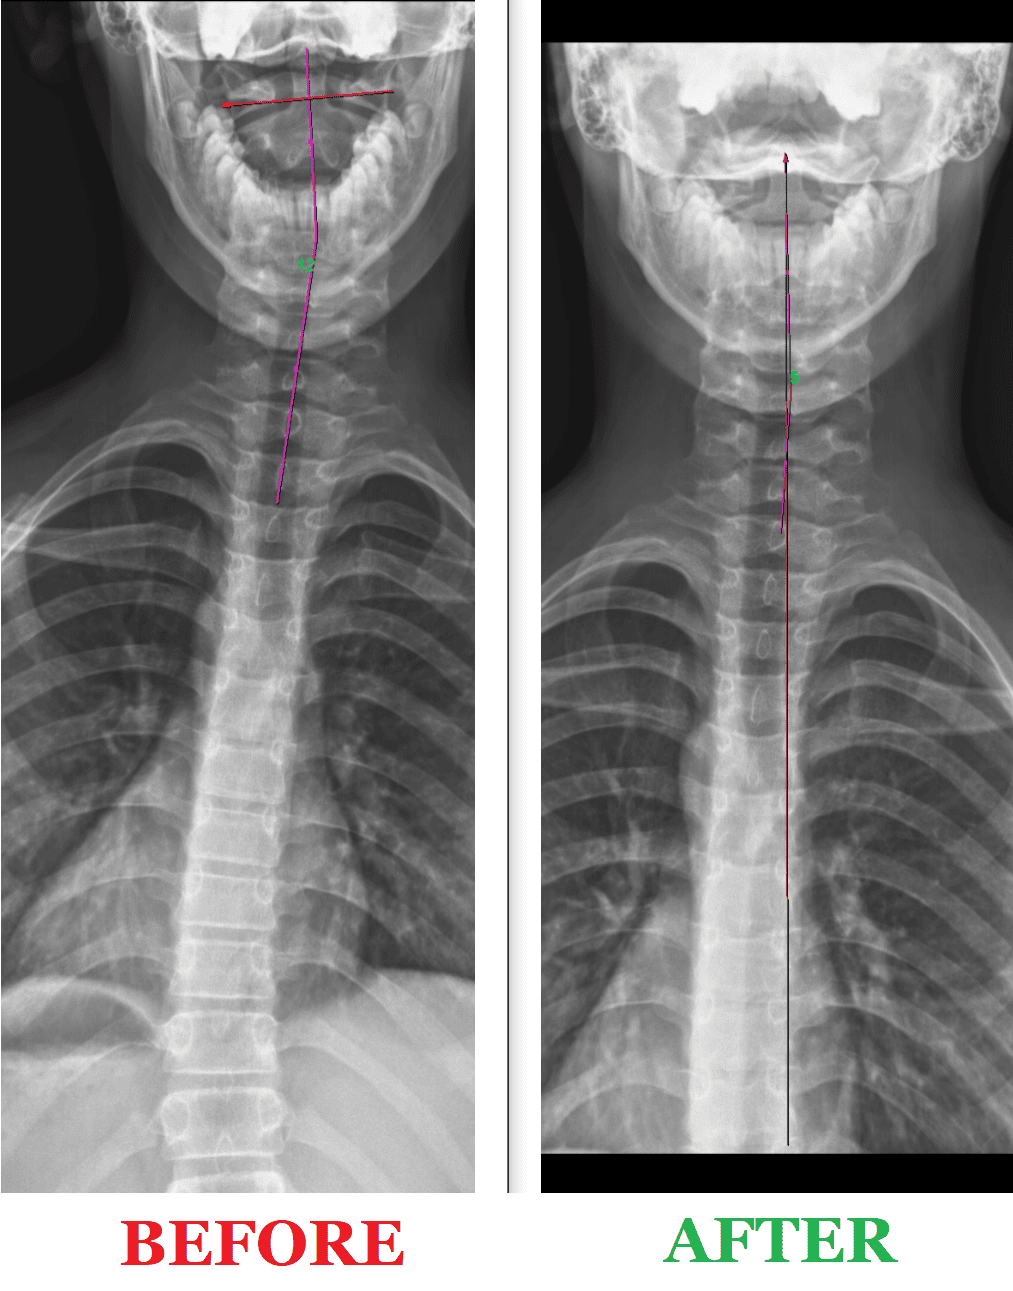

The Digital Posture X-Rays below are Before & After X-rays of practice members that got AMAZING RESULTS via our Corrective Care health program over the course of just 1 year!

By taking digital spine x-rays, chiropractors at Camarata Chiropractic can identify problems with the spine's alignment, detect bone density changes, and assess the degree of degeneration that may exist. This information helps chiropractors to identify underlying causes of spinal misalignment, such as injury or degeneration, and develop a treatment plan that addresses these issues. With the help of digital spine x-rays, chiropractors can also monitor the effectiveness of treatment over time, making any necessary adjustments to ensure that patients receive the best possible care.